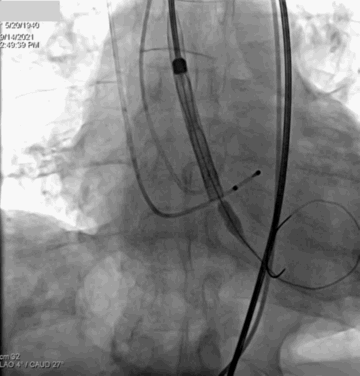

手术策略:右侧股动脉为主入路,左侧辅助入路。选用20mm球囊行预扩张,预扩角度为左冠切线位(LAO 28° CRA 1°)。预装AV26瓣膜,由于左右重合体位太大,瓣膜释放体位采用无冠窦最低法,调整至(LAO 4° CAU 27°),释放深度控制在2-4mm。

主动脉根部造影

20mm球囊预扩

输送器过弓

瓣膜系统跨瓣

瓣膜释放

瓣膜精准定位

瓣膜流畅释放至功能位

瓣膜完全释放

右足位造影